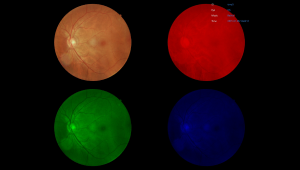

Вбудовані фільтри

FundusVue предоставляет фильтры без красного, негативную пленку, RGB, градации серого, чтобы пользователи могли изменять или применять фотоэффекты к изображению для различных целей.